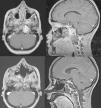

ResultadosCatorce pacientes (hombre/mujer 2:1) con una media de edad de 49años en los cordomas y de 32años en los condrosarcomas. La presentación clínica más frecuente fue la diplopía (78,5% de los casos), seguida de la disfagia (28,6%). Histológicamente se reportaron como cordomas el 71,4% y como condrosarcomas el 28,6%. Además, se encontró en el 81% de los casos invasión de al menos dos o más tercios del clivus, en el 57,1% invasión intradural y en el 35,7% invasión sellar. En el 42,8% de los casos el grado de resección fue total y en el 21,5%, subtotal. La complicación más frecuente fue la fístula de LCR, que se presentó en el 28,6% de los casos, habiendo que intervenir solo a un paciente. En el 35,7% de los casos se indicó tratamiento coadyuvante con Proton Beam y en el 21,5% radioterapia convencional. La media de seguimiento fue de 53,5meses, y se encontró recurrencia o progresión tumoral en el 21,5% de los casos, dos de los cuales no había recibido coadyuvancia. No hubo fallecimientos.

ResultsWe had fourteen patients (male/female 2:1), with a mean age of 49years for chordoma and 32 for chondrosarcoma. The most common clinical presentation was diplopia in 78.5% of cases, followed by dysphagia in 28.6%. Histologically, 71.4% were chordomas and 28.6% were chondrosarcomas. In addition, invasion of at least two thirds or more of the clivus was found in 81% of the cases; in 57.1% there was intradural invasion, and in 35.7% invasion of the sella turcica. In 42.8% of cases, the degree of resection was total and in 21.5% subtotal. The most common complication was CSF fistula, occurring in 28.6% of the cases, with only one case requiring surgery to repair it. Adjuvant treatment with Proton Beam was performed in 35.7% of cases and with conventional radiotherapy in 21.5%. Mean follow-up was 53.5months and tumour recurrence or progression was found in 21.5% of the cases, two of which had not received adjuvant treatment. There were no deaths.